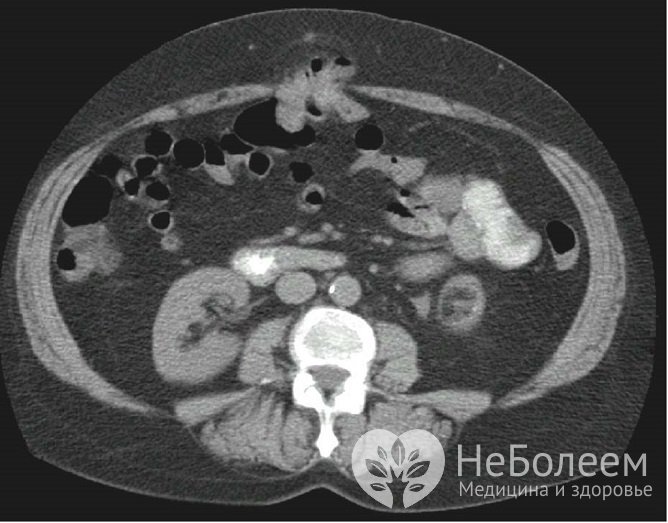

Пупочная грыжа на компьютерной томографииДиагностика эмбриональных пупочных грыж в большинстве случаев осуществляется еще в антенатальном периоде при проведении ультразвукового исследования плода.